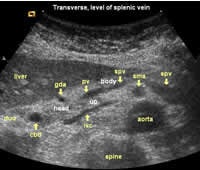

The following study describes anatomical landmarks in the ordinary pancreas of a thin patient:

Transverse planes in caudal direction:

![]() Image01 |